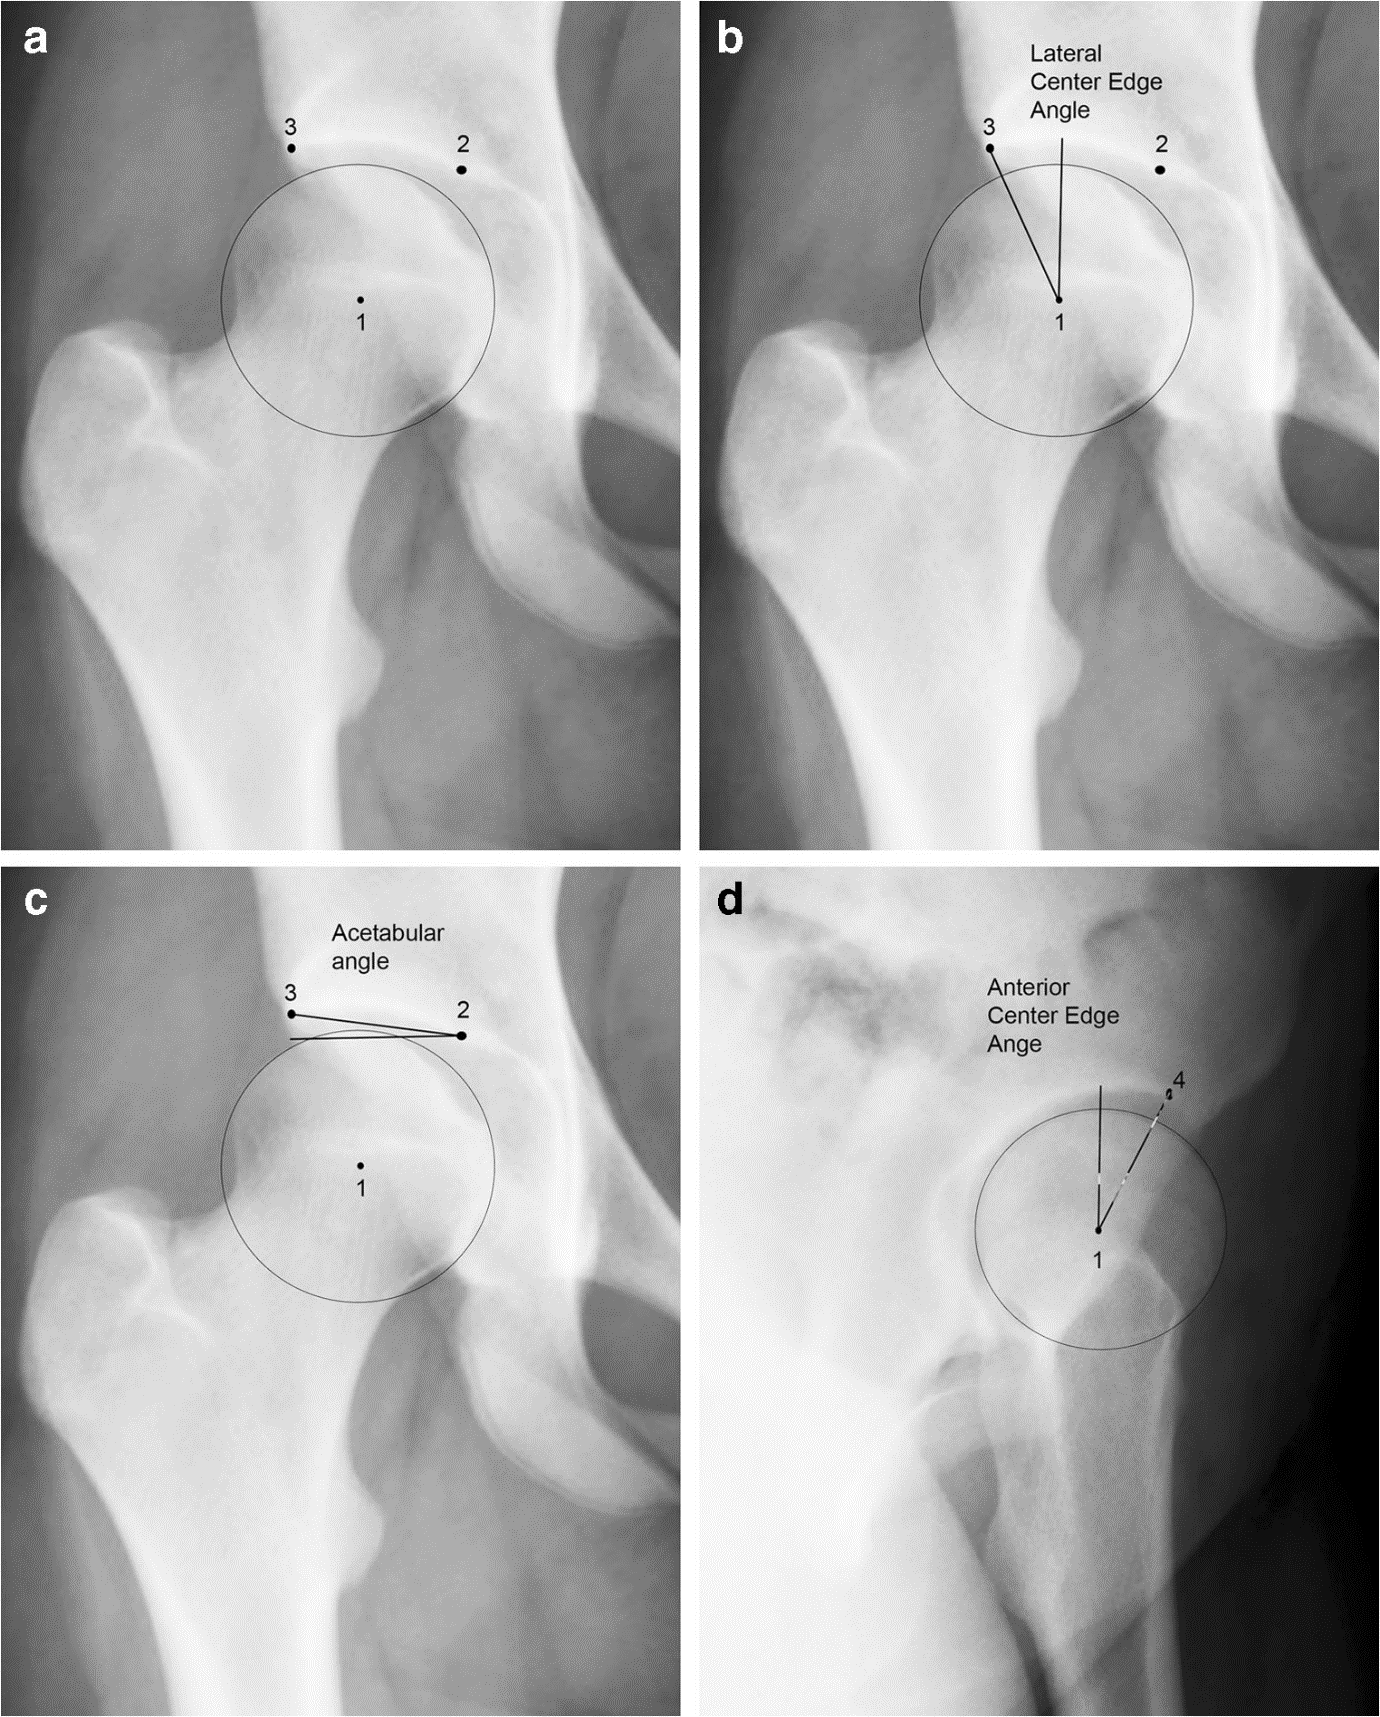

臨界髖關節(jié)發(fā)育不良BorderlineDDH:什么時候、怎么判定為異常?作者:SarahDBixby,MichaelBMillis.作者單位:DepartmentofRadiology,BostonChildren'sHospital,Main2,300LongwoodAve.,Boston,MA,02115,USA.sarah.bixby@childrens.harvard.edu.譯者:陶可(北京大學人民醫(yī)院骨關節(jié)科)摘要臨界髖關節(jié)發(fā)育不良是指髖臼形狀和覆蓋范圍輕度低于正常范圍,可能導致兒童易患機械功能障礙和不穩(wěn)定。臨界發(fā)育不良通常包括外側中心邊緣角(CEA)為18-24°的兒童。一些具有臨界X線測量值的兒童具有正常的關節(jié)力學和功能,而其他兒童則需要進行髖臼截骨手術。雖然臨界髖關節(jié)發(fā)育不良的X線檢查結果可能表明不穩(wěn)定,但最終診斷基于病史和體格檢查以及影像學相結合?;加信R界髖關節(jié)發(fā)育不良的兒童有時還需要進行其他橫斷面成像研究,如MRI成像,以評估不穩(wěn)定的次要證據(jù),包括沿髖臼邊緣的損傷或盂唇退化和肥大。CT也有助于描繪3-D髖臼形態(tài),以進行術前評估和規(guī)劃。兒童放射科醫(yī)生通常是第一個在X線片上發(fā)現(xiàn)邊緣性或輕度發(fā)育不良的人。兒童放射科醫(yī)生必須充當有效的顧問,并作為針對這一復雜患者群體的連貫多學科診療團隊的一部分提供適當?shù)慕ㄗh。圖1?一名16歲女孩的髖關節(jié)X線片顯示了外側中心邊緣角(CEA)、髖臼指數(shù)和前CEA的測量方法。a標記了三個點以便進行后續(xù)測量:點1位于股骨頭(旋轉)中心,點2位于股骨髖關節(jié)(負重關節(jié)面的)內(nèi)側邊緣,點3位于股骨髖關節(jié)(負重關節(jié)面的)外側邊緣。b右髖關節(jié)的前后位X線片展示了測量外側CEA的方法。外側CEA是連接點1和點3的線與垂直線之間形成的夾角(正常為25-40°)。c髖臼指數(shù)由連接點2和點3的線與水平線之間形成的夾角決定(正常為0-10°)。d右髖關節(jié)的假斜位片顯示了確定前CEA的測量方法。前側CEA由點1到點4(在髖臼前緣)的連線與垂直線之間的角度決定(正常值為25–40°)圖2?一名19歲女性嚴重雙側髖關節(jié)發(fā)育不良。a骨盆前后位X線片顯示右側髖關節(jié)外側中心邊緣角(CEA)為5°,b髖臼指數(shù)為16°。左髖關節(jié)同樣發(fā)育不良。c右髖關節(jié)假斜位X線片顯示前方中心邊緣角為8°。圖3?一名右側髖關節(jié)疼痛的16歲女孩的外側中心邊緣角(CEA)。a前后位(AP)骨盆X線片顯示外側CEA為19°。左側髖關節(jié)正常。b同一女孩的假斜位X線片顯示前方CEA為19°。c延遲釓增強軟骨MRI(dGEMRIC)檢查的冠狀T1圖顯示軟骨正常。女孩沒有不穩(wěn)定的跡象,接受了腰肌勞損治療,癥狀在沒有手術的情況下得到改善。由于腰肌勞損仍然可能與潛在的微不穩(wěn)定有關,女孩在髖關節(jié)外科醫(yī)生的護理下接受長期觀察。圖4?一名有髖關節(jié)發(fā)育不良家族史的11歲女性足球運動員的左側髖關節(jié)疼痛。a前后位(AP)X線片顯示為正常。b女孩現(xiàn)在13歲,仍然有左側髖關節(jié)疼痛。雙側髖關節(jié)被認為是淺的,左側測量的外側中心邊緣角(CEA)為16°,右側為23°。左側髖臼指數(shù)也被認為是升高的13°。陽性恐懼測試反映了體格檢查中左側髖關節(jié)的不穩(wěn)定,右側沒有發(fā)現(xiàn)不穩(wěn)定。C假斜位X線片顯示前方覆蓋充分,前方CEA為27°。d左側髖臼周圍截骨術后前后位AP骨盆X線片狀態(tài)顯示側方覆蓋改善。女孩報告癥狀有所改善。e一年后的前后位AP骨盆X線片,癥狀緩解并恢復正?;顒?。她右側有輕微間歇性疼痛,并定期監(jiān)測癥狀。圖5?股骨骨骺髖臼頂(FEAR)指數(shù)。a與圖1中相同的16歲女孩的髖關節(jié)前后位(AP)X線片。FEAR指數(shù)是沿髖臼頂連接點2和點3的線(黑線)與沿股骨骨骺線中央三分之一繪制的線(白線)之間形成的角度。陽性FEAR指數(shù)定義為向外側傾斜的角度,頂點指向內(nèi)側。這個女孩的FEAR指數(shù)小于5°。與FEAR指數(shù)<5°相比,F(xiàn)EAR指數(shù)>5°與不穩(wěn)定性具有更大的相關性。b一名13歲女孩的髖關節(jié)前后位X線片顯示左側髖臼外側輕微上翻(箭頭)。c一名13歲男孩的右側髖關節(jié)疼痛的左側髖關節(jié)正常前后位X線片顯示外側正常。黑線表示髖臼頂部,白線表示骨骺線的中央三分之一。此正常髖關節(jié)的FEAR指數(shù)顯示FEAR指數(shù),角度頂點指向外側。圖6?一名18歲女子田徑運動員的右側髖關節(jié)疼痛影像。a前后位(AP)骨盆X線片顯示右側髖關節(jié)發(fā)育不良,左髖關節(jié)正常。b右側髖臼周圍截骨術后前后位(AP)骨盆狀態(tài)顯示外側覆蓋增加,但該女性報告癥狀惡化。c術前(回顧性)進行的右髖關節(jié)矢狀質子密度脂肪抑制MR圖像顯示前髖臼內(nèi)有骨樣骨瘤(箭頭)。射頻消融后,該患者的癥狀得到緩解。?Theborderlinedysplastichip:whenandhowisitabnormal?AbstractBorderlineacetabulardysplasiareferstomildlysub-normalpatternsofacetabularshapeandcoveragethatmightpredisposechildrentomechanicaldysfunctionandinstability.Borderlinedysplasiagenerallyincludeschildrenwithalateralcenteredgeangle(CEA)of18-24°.Somechildrenwithborderlineradiographicmeasurementshavenormaljointmechanicsandfunctionwhileothersbenefitfromacetabularreorientingsurgery.Althoughradiographicfindingsofborderlinedysplasiamightsuggestinstability,theultimatediagnosisisbasedonhistoryandphysicalexaminadditiontoimaging.Childrenwithborderlineacetabulardysplasiasometimesbenefitfromothercross-sectionalimagingstudiessuchasMRimagingtoevaluateforsecondaryevidenceofinstability,includingdamagealongtheacetabularrim,orlabraldegenerationandhypertrophy.CTisalsohelpfulfordepictionof3-Dacetabularmorphologyforpreoperativeassessmentandplanning.Pediatricradiologistsareoftenthefirsttoidentifyborderlineormilddysplasiaonradiographs.Itisimperativethatpediatricradiologistsserveaseffectiveconsultantsandofferappropriaterecommendationsaspartofacohesivemultidisciplinaryapproachtothiscomplexpatientpopulation.Fig.1Radiographsofthehipina16-year-oldgirldemonstratemeasurementtechniqueforlateralcenteredgeangle(CEA),acetabularindex,andanteriorCEA.aThreepointsaremarkedforsubsequentmeasurements:Point1atthecenterofthefemoralhead,Point2atthemedialedgeofthesourcil,Point3atthelateraledgeofthesourcil.BAnteroposteriorpelvicradiographconeddowntotherighthipdemonstratestechniqueformeasuringlateralCEA.ThelateralCEAistheangleformedbetweenthelineconnectingPoint1toPoint3andaverticalline(normal25–40°).cAcetabularindexisdeterminedbytheangleformedbetweenalineconnectingPoint2toPoint3andahorizontalline(normal0–10°).dFalseprofileviewoftherighthipdemonstratesmeasurementtechniquefordetermininganteriorCEA.AnteriorCEAisdeterminedbytheanglebetweenalinefromPoint1toPoint4(attheanteriormarginofthesourcil)andaverticalline(normal25–40°)Fig.2Severebilateralhipdysplasiaina19-year-oldwoman.aAnteroposteriorradiographofthepelvisdemonstratesalateralcenteredgeangle(CEA)oftherighthipof5°and(b)acetabularindexof16°.Thelefthipissimilarlydysplastic.cFalseprofileradiographoftherighthipdemonstratesanteriorcenteredgeangleof8°.Fig.3Borderlinelateralcenteredgeangle(CEA)ina16-year-oldgirlwithrighthippain.aAnteroposterior(AP)pelvisradiographrevealsborderlinelateralCEAof19°.Thelefthipisnormal.bFalseprofileradiographofthesamegirlrevealsanteriorCEAof19°.cCoronalT1mapfromdelayedgadolinium-enhancedMRIofcartilage(dGEMRIC)examinationrevealsnormalcartilage.Thegirldidnothavesignsofinstability,wastreatedforpsoasstrain,andsymptomsimprovedwithoutsurgery.Becausepsoasstraincouldstillberelatedtounderlyingmicroinstability,thegirlwasunderlong-termobservationundercareofahipsurgeon.Fig.4Lefthippaininan11-year-oldfemalesoccerplayerwithafamilyhistoryofhipdysplasia.aAnteroposterior(AP)radiographinterpretedasnormal.bGirlnowisage13years,stillwithlefthippain.Bilateralhipswereconsideredshallow,withlateralcenteredgeangle(CEA)measuredat16°ontheleftand23°ontheright.Acetabularindexontheleftwasalsoconsideredelevatedat13°.Positiveapprehensiontestreflectedinstabilityofthelefthiponphysicalexamination,withnoinstabilitynotedontheright.cFalseprofileradiographrevealsadequateanteriorcoverage,withanteriorCEAof27°.dAPpelvisradiographstatuspostleft-sideperiacetabularosteotomydemonstratesimprovedlateralcoverage.Thegirlreportedimprovedsymptoms.eAPpelvisradiograph1yearlater,afterreliefofsymptomsandreturntonormalactivity.Shehadmildintermittentpainontherightandwasbeingmonitoredperiodicallyforsymptoms.Fig.5Femoro-epiphysealacetabularroof(FEAR)index.AAnteroposterior(AP)radiographofthehipinthesame16-year-oldgirlasinFig.1.TheFEARindexistheangleformedbetweenalineconnectingPoint2andPoint3alongtheacetabularroof(blacklines),andalinedrawnalongthecentralthirdofthefemoralphysealscar(whiteline).ApositiveFEARindexisdefinedbyalaterallydirectedanglewiththeapexpointingmedially.TheFEARindexinthisgirlislessthan5°.AFEARindex>5°hasagreatercorrelationwithinstabilitycomparedtoFEARindex<5°.bAPradiographofthehipina13-year-oldgirlwithmildleftacetabularsourcildemonstratesamildlyupturnedlateralsourcil(arrow).cNormalAPradiographofthelefthipina13-year-oldboywithrighthippaindemonstratesanormallateralsourcilforcomparison.Theblacklineindicatestheacetabularroofandthewhitelineindicatesthecentralthirdofthephysealscar.TheFEARindexisdemonstratedinthisnormalhiptoillustrateanegativeFEARindexwiththeapexoftheangledirectedlaterally.Fig.6Imaginginan18-year-oldfemaletrackathletewithrighthippain.aAnteroposterior(AP)pelvisradiographreportedasborderlinerightacetabulardysplasiaandnormallefthip.bAPpelvisstatuspostrightperiacetabularosteotomydemonstratesincreasedlateralcoverage,thoughthewomanhadreportedworseningsymptoms.cSagittalproton-densityfat-suppressedMRimageoftherighthipperformedpreoperatively(retrospectively)revealsanosteoidosteomawithintheanterioracetabulum(arrow).Thewoman’ssymptomsresolvedafterradiofrequencyablation.?AdvancinginvestigationTheterm“borderlinedysplasia”isalsofallingoutoffavor.Advancedimagingmodalitieshaverevealedpatternsofdysplasiathatarenotapparentonradiographs.FocalanteriorandposteriordysplasiagroupshaveanormallateralCEAontheAPradiograph[9].Refinedandupdatedradiographicmeasurementshavebeenproposedthatwouldenablebetteridentificationofchildrenwithfocaldysplasia,suchastheanteriorwallindexandposteriorwallindex[48].Earlystudiesdemonstrateddifferencesintheanteriorandposteriorwallindicesinsymptomaticdysplasticpatientscomparedtothosewithanormalacetabulum[48].Subsequentinvestigationrevealedthatevenasymptomaticpeoplehaveradiographicanteriorandposteriorwallindexmeasurementsthatoverlapthoseofpeoplewithdysplasia[49].Thisindicatesthatsomedegreeofvariationinthe3-Dmorphologyoftheacetabulumisnormal.Furthervalidationoftheseindiceswithcross-sectionalimagingandlongitudinalfollow-upisnecessarybeforethesenewreferencestandardscanbeconsideredreliableindicatorsofdisease.Inthepresenceofinstabilityrelatedtoacetabulardysplasia,thereisoftenovergrowthofsoft-tissuestructuresthatcompensatesforthedeficientbonysupport.Thisincludesenlargementoftheacetabularlabrum[50,51],evenintheabsenceoflabraltearordegeneration.Focalmuscleenlargementhasalsobeennotedinunstablepatients,specificallytheiliocapsularismuscle[52].MRImightbeusefulinidentifyingthesesecondarysignsofinstability.Still,noclearlypositivefindingsconfirmthepresenceofinstability.Femoralversionisalsoakeycomponentindetermininghipstability,asanantevertedfemurisbemoreanteriorlyuncoveredthananeutralfemur[53].Overtfeaturesofacetabularrimdamagealsosupportthediagnosisofdysplasia,includinglabraldegenerationandtearingandcartilageloss,thoughadolescentswhohaveborderlinedysplasiamightnotyethavevisiblemanifestationsofosteoarthritis,evenifinstabilityisthepaingenerator.Giventheseareasofinvestigationanduncertainty,theborderlinedysplastichiphasattractedwell-deservedattentionintheliterature.Specificconcernshavebeenraisedaroundwhethertheterm“borderlinedysplasia”isanadequatelabelandwhetherthisisasinglecondition.ItismorelikelythatchildrenwithaborderlinelateralCEAof18–24°consistofclustersofpatients,someofwhommighthavecamimpingement,andsomeofwhomhavefocalacetabulardeficiency[13].Specificpatternsofacetabulardeficiencyandfemoralmorphologyarebestcharacterizedwithcross-sectionalimagingexaminations,suchasMRIorCT,whichmightalsodetectothercausesforhippain.ItisrecommendedthatanychildinwhomthereisconcernfordysplasiaundergoanMRIaspartofacompleteevaluationbecausetheremightbeanotherfindingthatexplainsthechild’ssymptoms(Fig.6),orevidenceofintra-articulardamagethatsupportsrimloading.MRIiswellsuitedfordetectingcartilageandlabralabnormalitiesaswellasmarrowlesionsthatarepresentinthesettingofalteredbiomechanicsandearlyosteoarthritis[8].Low-dosepelvicCTisalsovaluableforpreoperativeassessmentofthehipmorphologywithprecisecharacterizationofthebonydeficienciesinthreedimensions.Itiscrucialthatthesechildrenaredirectedtoanexperiencedhipspecialistwhoisabletocontextualizetheimagingfindingswithacomprehensivephysicalexamandanappropriatehistory.Thesechildrenshouldbeinterrogatedwithrespecttothenatureandlocationoftheirpainwithspecificquestionsaroundinstability.Acomprehensivephysicalexamshouldfollow,includingattentiontothechild’sgait,pelvicpositionandrotationalprofile.ConclusionTheterm“borderlinedysplasia”referstopatternsofacetabularcoveragethatmightpredisposechildrentoinstability.Somechildrenwithborderlineradiographicmeasurementshavenormaljointmechanicsandfunction(Fig.1ShouldsayFigure3),whileothersbenefitfromacetabularreorientingsurgery(Fig.2ShouldsayFigure4)[11].Itisimportantthatradiologistsreflectthisuncertaintyintheirreportswithappropriatemanagementrecommendations.Instabilitymightbesuggestedbyradiographs,butultimatediagnosisisconfirmedonthebasisofhistoryandphysicalexamassessingforinstability.Thesechildrenshouldundergohigh-resolutionMRimagingofthehiptoevaluateforjointdamage,andCTmightbehelpfulforbetter3-Dcharacterizationofthebonyshapeandcontour.Dynamicultrasonographyhasbeenvalidatedasahelpfuladjunctinthedeterminationofinstabilitybymeasuringanteriorfemoralheadtranslationwithdynamicmaneuversreplicatingtheapprehensiontest[54].Aspediatricradiologists,weareoftenthefirsttoidentifyborderlineormilddysplasiaonthebasisofradiographs.Itisimperativethatweserveaseffectiveconsultantsandofferappropriaterecommendationsaspartofacohesivemultidisciplinaryapproachtothiscomplexpatientpopulation.?文獻出處:SarahDBixby,MichaelBMillis.Theborderlinedysplastichip:whenandhowisitabnormal?ReviewPediatrRadiol.2019Nov;49(12):1669-1677.doi:10.1007/s00247-019-04468-4.Epub2019Nov4.??IntroductionDevelopmentalhipdysplasia(DDH)isoneofthemostimportantandmostcommonpediatricmusculoskeletalconditions.Whileasmanyas80%ofcasesarepresentatbirth,manyremainundiagnosed.Whenpresentininfancy,DDHmightbedetectedonthebasisofphysicalexaminationfindings(i.e.BarlowandOrtolanimaneuvers)andstaticanddynamicultrasoundfeaturesoriginallydescribedbyGraf[1,2].Thelong-termimplicationsofDDHaresignificantbecausetheconditionleadstodevelopmentofosteoarthritisin25–50%ofpatientsbytheageof50years[3].Thereducedsizeandtheincreasedobliquityoftheacetabularweight-bearingsurfacecreateshearingforcesonthearticularcartilageandcausechronicoverloadingoftheanteriorandanterolateralacetabularrim[4].Thismechanicaldysfunction,ifuncorrected,leadsinadulthoodtopain,abductorfatigueandoftensymptomsofinstability,culminatingingradualfailureofthecartilageandleadingtoprogressiveosteoarthritis.Treatmentstrategiesdependonthemechanicalstabilityofthehipandthetypeanddegreeofbonydeformity.IninfantswithmildDDH,capsularlaxityandmildacetabulardysplasiaaretheissues,andsimplepositioningofthehipsinabductionandflexioninaprotectivebraceorPavlikharnessusuallyleadstotighteningofthecapsuleandresolutionofthedysplasia.Inchildrenwithfullcongenitaldislocations,particularlyifdiagnosedafterinfancy,aformalmanipulativereductionmightberequired,withspicacastingforseveralmonths.Atanyage,treatmentisfocusedonreducingandmaintainingthefemoralheadtoaconcentricpositionwithintheacetabulum.IfbonymalalignmentispresentintheolderchildwithDDH,realignmentsurgeryisoftenneededtorestorestability.Infantsandchildrenwithdevelopmentalhipdysplasiamightbetreatedtocurebyvirtueoftheseearlystrategies,ortheymighthavepersistentsubluxationthatrequiresfurthersurgerylaterinadolescenceoryoungadulthood.DysplasiainadolescentsAdolescentsandyoungadultswhohadbeenasymptomaticwithrespecttothehipmightalsohavemildformsofacetabulardysplasiadetectedonradiographsbasedoncriteriaoriginallydefinedbyWiberg(Figs.1and2)[5].Inmanychildrentheindicationforradiographsishippain,thoughforsomechildrenradiographsareperformedforotherindications.Intheabsenceofadedicatedexaminationbyahipspecialistwhocanassessforsignsorsymptomsofinstability,itisnotknownwhethermildorsubtleradiographicabnormalitiesarethesourceofthechild’ssymptoms.Radiographicmeasurementsoffemoralheadcoverageandpositionmightsuggestthepossibilityofmechanicaldysfunctionofthehip,thoughitisthemechanicsthatdefinetheunderlyingdisease,nottheradiographs.IncontrasttoinfantileDDH,adolescentdysplasiahasahighermalepredominanceandismoreoftenbilateral[6].Thedifferenceindemographicsbetweengroupshaspromptedmanytoquestionwhetheradolescentandinfantilehipdysplasiasaretwodistinctentities.Thestandinganteroposterior(AP)radiographofthepelvisremainsthegoldstandardofimagingforadolescenthipdysplasia,supplementedbyotherviewsincludingthefalseprofileradiograph[4].Anumberofradiographicmeasurementshavebeendescribedthatdefinethedysplastichip,thethreemostfundamentalincludingthelateralcenteredgeangle(CEA),theacetabularindexandtheanteriorCEA[7].ThelateralCEAandtheacetabularindexarebothmeasuredonaproperlypositionedstandingAPradiographofthepelvis,whereastheanteriorCEAismeasuredonthefalseprofileradiograph(Figs.1and2).In1939Wiberg[5]definedanormallateralCEAasbeingover25°,anabnormalangleaslessthan20°(Fig.2)andeverythinginbetweenasuncertain.Theserangeswerevalidatedinsubsequentinvestigations[8,9].SimilarcriteriaexistfortheanteriorCEAasmeasuredonafalseprofileradiograph,wherethisangleisconsiderednormalabove25°,borderlineat20–24°anddeficientbelow20°(Fig.2)[10].Incertainchildrentheanterioracetabularroofinsufficiencyismoreseverethanthelateralroofinsufficiency,andthefalseprofileviewmighthelptoidentifythesechildren,withthecaveatthattheanteriorCEAisthemostdependentonradiographictechnique[11].Theacetabularindexisconsiderednormalat0–10°[7],thoughsomehavesuggestedthatanglesupto13°arenormal[8].Valuesabovethisareconsideredindicativeofdysplasia.BorderlinemeasurementsWhilefloridacetabulardysplasiaisincontrovertiblewhenidentifiedradiographically(Fig.2),thecorrectdiagnosisbecomesmoredifficultwhenthemeasurementanglesareonlymildlyoutofthenormalrange,leadingtothecreationofan“uncertain”or“borderline”category(Figs.3and4).Thesechildrenremainasourceofconfusionandcontroversyamongradiologistsandhipspecialists.Ultimately,achildfallingintoanuncertaincategoryhaseitherahealthyoranunhealthyhip,andthisdistinctiondependsonavarietyoffactorsuniquetoeachchildthatgobeyondasimpleradiographicmeasurement.Thelabel“borderlinedysplasia”hasbeenadoptedtodefineagroupthatfallsintoanuncertainmeasurementcategorywithlateralCEAof18–24°[12–14],inwhomfurtherevaluationisnecessarybeforeadiagnosiscanbemade.Giventhemechanicalbasisforthejointdamageinacetabulardysplasia,itisareasonableassertionthathipswithslightlydiminishedcoveragearepredisposedtojointdamagerelatedtoincreasedwearontheacetabularrim.Childrenwithmilddysplasiaareknowntohaveevidenceoflabralandcartilagedamageathiparthroscopy[15].ThisdoesnotmeanthatallchildrenwithalateralCEAof18–24°developosteoarthritis.Earlystudiesevaluatingtherelationshipbetweencenteredgeangleanddysplasiafocusedprimarilyonhipfunctionratherthanspecificevidenceofjointdamage[16],thoughitislikelythatnormallyfunctionalhipsmightovertimealsohavelabraltearsandcartilagelesions.Delayedgadolinium-enhancedMRIofcartilage(dGEMRIC)measurementsDelayedgadolinium-enhancedMRIofcartilage(dGEMRIC)wasdevelopedtoidentifyhipswithearlybiomechanicaldamagetothecartilagematrixinadvanceofmorphologiccartilageloss[17].Whenintroducedviaintravenousorintraarticularinjection,ananionicmoleculesuchasgadopentetate?2(Gd-DTPA?2)distributesovertimeincartilageinverselytotheconcentrationofnegativelychargedglycosaminoglycans.TheconcentrationofGd-DTPA?2canbeindirectlydeterminedwithmeasurementsofT1andisexpectedtobelowerinnormalcartilagecomparedtodegradedcartilagewithlossofglycosaminoglycans.Thismeasurementisreferredtoasthe“dGEMRICindex”(Fig.3).EvaluationofthedGEMRICindexinpeoplewithnoormilddysplasiarevealedthatthedGEMRICindexofmildlydysplastichipsdidnotdiffersignificantlyfromthatofnormalhips[17].ItshouldbenotedthatinthisstudypeoplewithmilddysplasiaweredefinedbyalateralCEA>15°,whichislowerthanwhatwouldnowbeconsideredthethresholdofmilddysplasia.Thesedatasuggestthatchildrenwithmildorborderlinedysplasiamightnotbeatincreasedriskofdevelopingend-stageosteoarthritis,thoughbecausethesepeoplewerenotfollowedlongitudinallyovertimeitisunknownwhethercartilagedegenerationevolvedovertime.ThedGEMRICindexalsodoesnotaddresswhetherchildrenhavesignsorsymptomsofinstability,whichmightbewhatbringsthemtomedicalattention.RadiographiclandmarksMeasurementsobtainedfromconventionalradiographsrelyonidentificationofpreciselandmarks,includingthecenterofthefemoralhead,themedialmarginoftheacetabularsourcil,andthelateralmarginoftheacetabularsourcil(Fig.1).Thesourcilisnotalwayswell-defined,especiallyinchildrenyoungerthan15years.Inyoungerchildrenitisuncommonforthelateralmarginofthesourciltoalsobethelateralmarginoftheacetabulum,promptingsomeinvestigatorstodevelopa“modifiedlateralCEA”thatincludesonlythescleroticportionoftheacetabularsourcil.ThisisincontrasttothetraditionalCEA,whichismeasuredtothelateralacetabularmargin[18].Therangeofnormaldependsontechniquebecausethemodifiedanglehasalowerstandardrange(15–20°)comparedtothetraditionalangle.Withoutstrictattentiontoradiographiclandmarksthevariabilitybetweenmeasurementscanbeextreme[19–21].Themostreliablemethodistoautomatetheprocesswithcomputer-aidedsoftware,eitherbyincorporatingacomputerizedmeasurementprogram[22]orbystandardizingtheprojectionoftheradiograph[23].Unlessrigorouscriteriaarebeingusedformeasurement,amildlyabnormalmeasurementshouldnotbeconsideredamarkofdiseaseunlessthereareothercompellingimagingandclinicalfindings.Anadhocmeasurementperformedby“eyeballing”theradiographisunlikelytobeaccurate.Itisbesttomeasuremultipletimes,especiallyintheabsenceofcomputer-aidedsystems.NormalvariantsCrossoversignRadiologistsarewisetoproceedcautiouslyaroundthehip,giventhefrequencywithwhichpreviouslyreportedradiographicmeasurementsorfindingshavebeensubsequentlydeterminedtorepresentnormalvariants.AnexampleofthisisthecrossoversignontheAPpelvisradiographs.In2007itwasdemonstratedthatthepresenceofacrossoversignwasahighlyreliableindicatorofcranial(superioracetabular)anteversionoflessthan4°[24].Forreference,thesuperioraspectoftheacetabulumisantevertedapproximately10–14°.Atangleslessthan0°,theanteriorwallislateraltotheposteriorwall,leadingtothecrossoversignonradiographswherethetwowallsoverlap.ItbecamestandardforradiologistsandhipspecialiststocommentonthepresenceofacrossoversignonAPradiographsofthepelvisassuggestiveofacetabularretroversion.Inclinicalpractice,however,thesechildrendidnotalwayshavesignsorsymptomsofretroversion,nordidcross-sectionalimagingconfirmretroversion.Overtime,theliteraturerefutedanassociationbetweencrossoversignandclinicallyconfirmedacetabularretroversion.Evenasymptomaticchildrenwithouthipdiseaseorsymptomatologydemonstratedacrossoversignonawellpositionedradiograph,reflectingvariationsinpatientpositioningaswellasthevariablemorphologyoftheanteriorinferioriliacspine[25,26].CoxaprofundaInsimilarfashion,theterm“coxaprofunda”fellinandoutoffavoralmostasquickly.Coxaprofundaisdefinedaspresentiftheflooroftheacetabularfossaliesmedialtotheilioischialline.Itisconsideredanindirectsignofacetabularovercoverageofthefemoralheadandwasproposedasanimagingfeatureofpincer-typefemoroacetabularimpingementin2007[27].Withthisawareness,radiologistsreadilyofferedthisimagingfindingasevidenceofanunderlyingcondition:acetabularover-coverage.Overtime,coxaprofundawasclaimedtobeanormalradiographicfindingthatdoesnotsupportadiagnosisofpincerimpingement[28–30].CamdeformityFinally,thedefinitionof“cam”deformityinchildrenwithfemoroacetabularimpingementhasbeenasubjectofinterestanddebateformanyyears.Camlesionsarebonyprotuberancesalongthefemoralhead/neckjunctionthatimpingeagainsttheacetabularriminhipflexion.Themostobjectivemeansofmeasuringthesizeofacamdeformityisthealphaangle,anangleformedbyalineconnectingthecenterofthefemoralheadtothecenterofthefemoralneck,andalinefromthecenterofthefemoralheadtothepointatwhichthefemoralneckfallsoutsideabest-fitcirclearoundthehead.Intheearly2000sitwasacceptedthatchildrenwithanalphaangleintherangeof50°likelyhadcam-typefemoroacetabularimpingement(FAI)[31–34].OverthelastdecadetherehasbeenincreasingawarenessthatsomepreviouslydefinedcamlesionsinpeoplewithFAImightbepresentinasymptomaticpopulationswithnohipdisease[35–38].Moreoverapositiveimpingementtest,oftenassociatedwiththepresenceofanteriorFAI,hasbeendemonstratedinhealthyyoungadultswhomightnothaveFAI[39],makingthisanunreliableindicatorofdiseaseinisolationofotherevidence.RadiographictechniqueGiventhatourinterestinidentifyingandtreatingpainfulanddebilitatingdiseaseinchildrenmightoutpaceourunderstandingofnormalanatomicalvariation,radiologistsneedguidelinesforinterpretingradiographsthatrevealanuncertaindegreeoffemoralheadcoverage.Acautiousapproachwouldbetosuggestthepossibilityofborderlinehipdysplasiaandrecommendreferraltoahipspecialist.Thisrecommendationshouldbeperformedwhentheimagingfindingshavebeendeemedreliable,whichrequiresstrictadherencetoproperimagingtechnique.ThefollowingshouldbeassessedoneveryAPradiographofthepelvis:(1)Isthepelvistiltedorrotated?Asaguideline,thedistancebetweenthesuperioredgeofthepubicsymphysisandthecoccyxshouldbe1–3cm[40].(2)Howwelldefinedarethemeasurementlandmarks?Ifthereisdoubtastowherethelandmarksarelocated,themeasurementsarelikelytobeinaccurate.(3)Aremeasurementsperformedusingelectroniccalipersorwithavalidatedcomputer-assistedprogram?Ifperformedbyhand,havetheinitialmeasurementsbeenvalidatedwitharepeatattempt?(4)Isthepatientolderthan15years,andifnotisthemodifiedlateralCEAstandardbeingemployedratherthantheclassiclateralCEA?Theanswerstothesequestionshaveagreatimpactonthereportedmeasures.Iftheimagingtechniqueisadequateandthechildstillfallsintoanindeterminatecategoryoftheborderlinedysplastic(alateralCEAthatfallsbetween18°and24°),thisisstillonlythefirststepinacomplexdiagnosticprocess.Ourunderstandingofhipdiseasehasevolvedconsiderablyoverthelastdecade.Itisimpossibletoaccuratelycharacterizeallofthedifferentpatternsofinstabilityandunder-coveragewith2-Dradiographicviews.RelyingsolelyonthelateralCEAtodeterminenormalversusdeficientcoverageassumesalldysplasiaisglobal,orprimarilyinvolvesthesuperioracetabulum.Wenowknowthatatleastthreedistinctpatternsofacetabulardeficiencyexist:anterosuperior,global,andposterosuperiorinsufficiency[41],andAPradiographsarenotdesignedtodetectafocalanteriororposteriordeficiency.Thepresenceofborderlinedysplasiaonradiographsalsodoesnotconfirmthepresenceofinstability,whichisultimatelywhatleadstosymptomsandjointdamage.Thepresenceorabsenceofinstabilityorimpingementmustbedeterminedthroughcarefulhistoryandphysicalexam,aswellasfromstaticandpossiblydynamicimaging.Thefemoroepiphysealacetabularroof(FEAR)indexhasbeenproposedasausefulradiographicmarkerofinstability(Fig.5)[42].Anotherhelpfulradiographiccluetothepresenceofinstabilityistheupslopinglateralsourcilmargin[43].Alloftheseobservations,however,requirefurthervalidationbeforetheycanbeconsideredreliablemarkersofdisease.Wiberg[5]laidtheimportantgroundworkwithhisseminalarticledescribingthe“normal”lateralcoverageofthefemoralhead,andformanydecadesthoseassertionshavenotbeendisproved;subsequentinvestigationshaveonlysubstantiatedhisoriginalfindings[44–46],thoughthelowerendofthenormalthresholdhasshiftedmoretowardthedysplasticendofthespectrum.Largerpopulation-basedstudieshaverecentlysuggestedthattheserangesaregender-specificandthatmaleandfemalepatientsshouldnotbemeasuredagainstthesamestandard.UpdatedreferencestandardsproposedbyLaborieetal.[39]suggestedthatcutoffvaluesformalepatientsshouldbe21°comparedto20°infemalepatients.Updatedupperthresholdvaluesforacetabularindexaccordingtothisstudywere15°formalesand16°forfemales,comparedtopreviouspublishedthresholdof10°forbothgroups.Accordingtothesenewcriteria,manypatientswhohadpreviouslybeencharacterizedasmildlyorborderlinedysplasticmightnowbeconsiderednormal.Additionally,age,gender,heightandbodymassindex(BMI)havebeenfoundtobefactorsinwhatareconsideredtobenormalrangesofacetabularcoverage,shiftingthelowerrangeofnormalcoveragefurtherintothedysplasticrangeforcertainpopulations[47].?